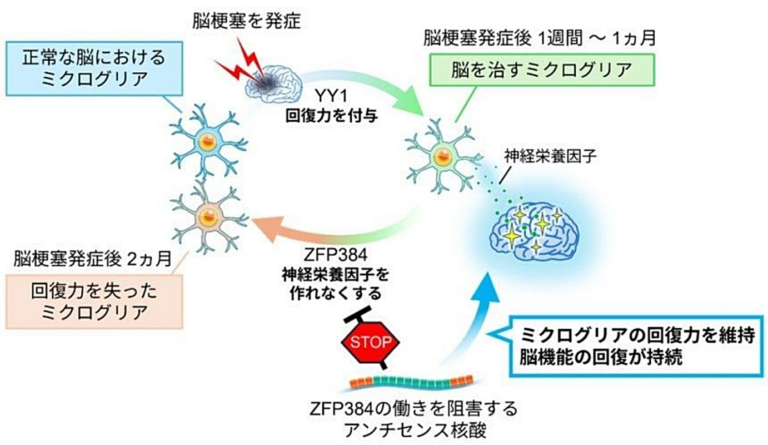

「脳梗塞は治らない」はもう古い?…寝たきりリスクに光を当てた“回復力”の正体

東京科学大学の研究チームが脳梗塞後の脳機能回復を助けるメカニズムを解明し、新たな治療法の可能性を示唆。

寝る前の“ひとつかみ”で腸内に変化?…糖尿病予備軍の研究で見えた「ピスタチオ」の意外な効果 ピスタチオが腸の健康に良い影響を与えることが研究で示され、糖尿病予備群の改善に役立つ可能性があると報告された。 「脳梗塞は治らない」はもう古い?…寝たきりリスクに光を当てた“回復力”の正体 東京科学大学の研究チームが脳梗塞後の脳機能回復を助けるメカニズムを解明し、新たな治療法の可能性を示唆。

「脳梗塞は治らない」はもう古い?…寝たきりリスクに光を当てた“回復力”の正体 東京科学大学の研究チームが脳梗塞後の脳機能回復を助けるメカニズムを解明し、新たな治療法の可能性を示唆。 コメの保存方法を誤ると”発がん性物質”が発生?…安全に保存する方法とは コメの保存方法を見直すことで、カビや害虫の発生を防ぎ、品質を保つことができます。